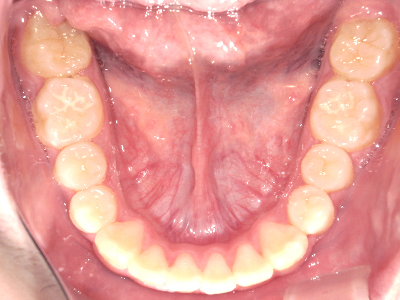

↓ - 下あごが狭くなる・下あごの位置が悪くなる

↓ - さまざまな不正咬合が生じる

ないき歯科クリニックでは、上あごの成長不足を補い、鼻呼吸を獲得しつつ歯列を整え、将来のお口をより健康な状態にすることをゴールに定める矯正治療をおこなっています。